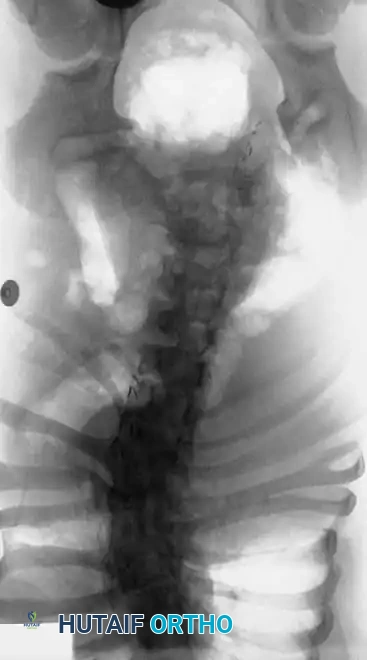

Image

Radiographic examples of progressive congenital curves requiring early intervention.

Surgical planning and execution of complex congenital curve corrections.